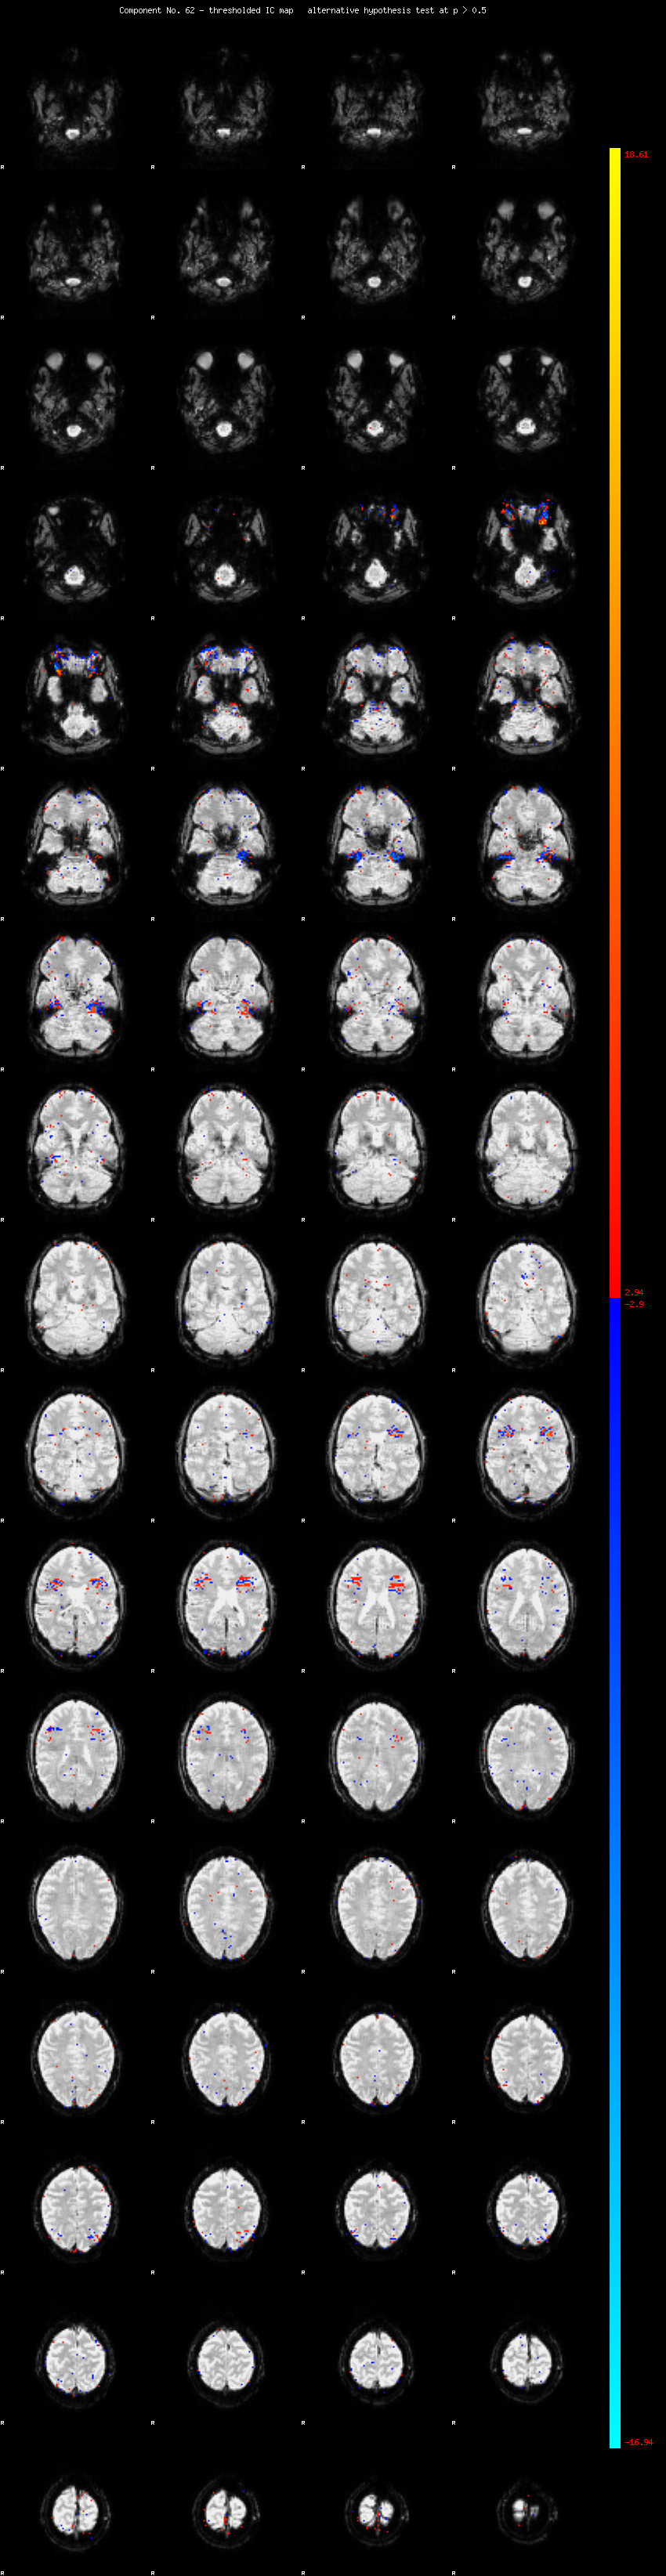

MELODIC Component 62

0.85 % of explained variance;     0.56 % of total variance